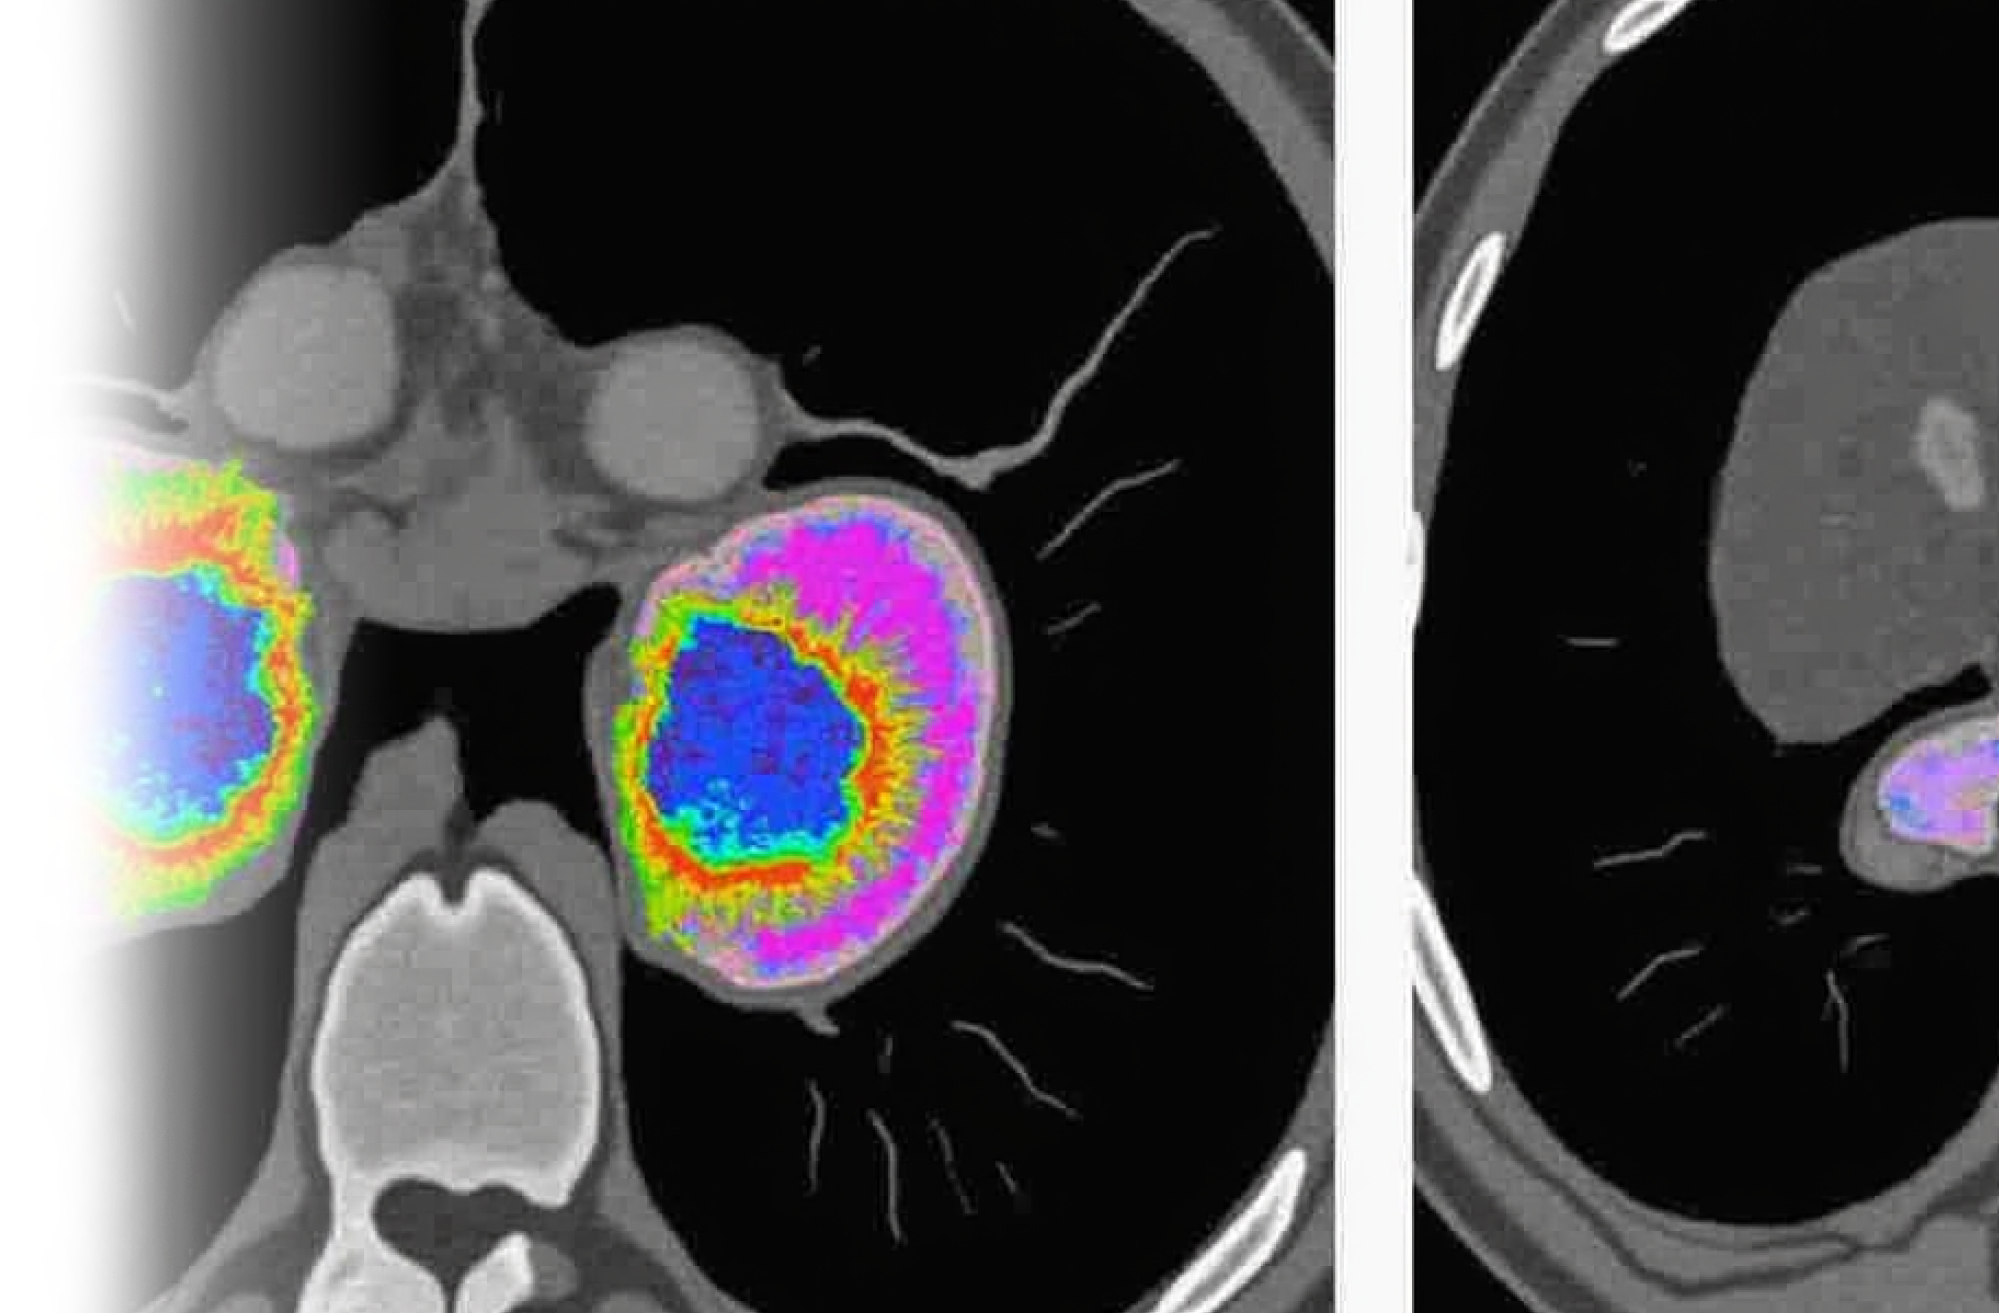

Компьютерная томография почек и надпочечников – важный метод прицельного исследования состояния почек и надпочечников.

Показания для проведения КТ почек и надпочечников:

• гиперплазия;

• узловые образования надпочечников;

• конкременты в полостной системе почек.